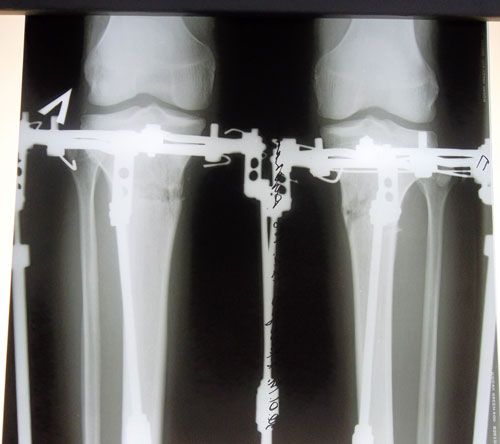

рентген в 16 дней после операции